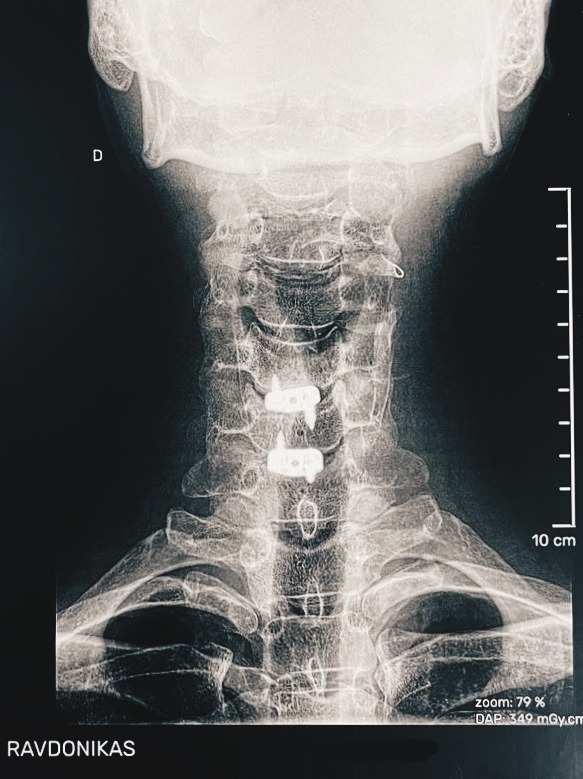

/ 9. Le Roi is fixed... /

Then this: the tempests

of your hormones calmed,

a careful peace — not

ceasefire! — with the meds.

Your head sits higher

by a couple millimeters,

two of your disks replaced

with cages of titanium,

both filled with artificial bone.

No pain.

A cut across your neck

is scheduled for removal

of its stitches and your new

spine for X-ray, a checkup —

then, you're back upon

the board.